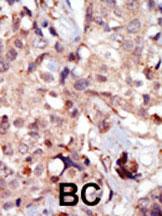

IHC 1/100-1/500 Human,Mouse,Rat

3. **文献名称**: "MLCK isoform-specific localization in human colorectal cancer tissues"

**摘要**: 通过免疫组化结合N-term MLCK抗体,该研究揭示了长链MLCK(MLCK210)在结肠癌组织中的异常高表达,并与肿瘤侵袭性正相关,为癌症治疗靶点提供了依据。